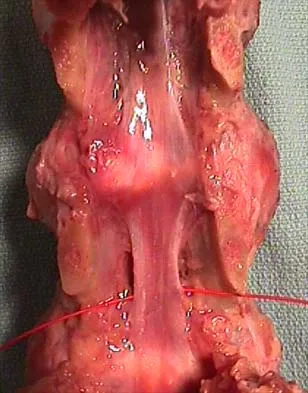

When performing a bunionectomy with a release of the lateral soft-tissue structures, the surgeon is cautioned against releasing the conjoined tendon that inserts along the lateral base of the proximal phalanx of the great toe. This conjoined tendon is made up of what two muscles?

Owens and Thordardson cautioned surgeons not to release the conjoined tendon from the base of the proximal phalanx of the great toe because of an increased risk of iatrogenic hallux varus. Release of the transverse and oblique heads of the adductor hallucis is largely accomplished by releasing the soft tissue adjacent to the lateral sesamoid, without releasing tissue from the base of the proximal phalanx. The conjoined tendon is made up of the flexor hallucis brevis and the adductor hallucis. Owens S, Thordardson DB: The adductor hallucis revisited. Foot Ankle Int 2001;22:186-191.